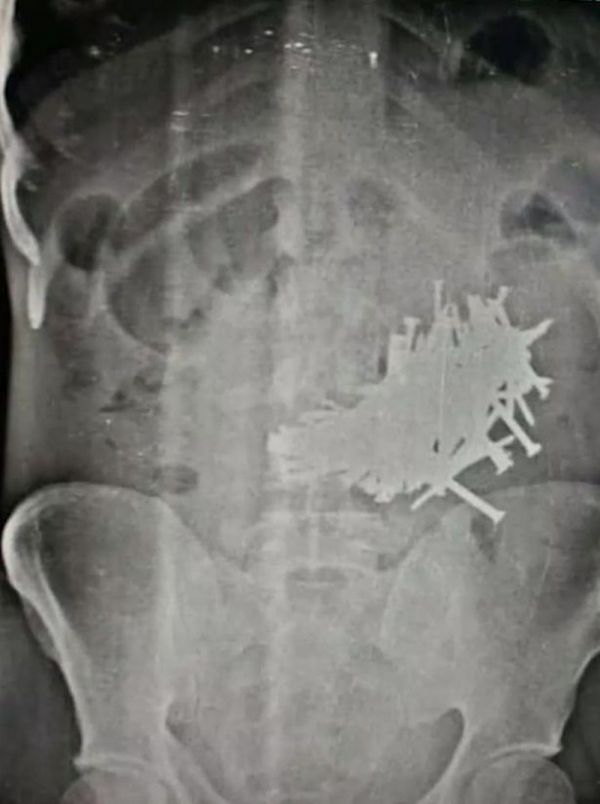

В больницу индийского штата Раджастхан доставили 43-летнего Бхола Шанкар, страдающего от сильных болей в животе. Оно и не удивительно — рентген показал наличие в его кишечнике огромного количества гвоздей.

Во время операции хирурги вытащили из него 116 гвоздей (каждый длиной более 5 см). Бхола считал свое патологическое пристрастие глотать гвозди шизофренией, а потому до последнего скрывал свои гастрономические предпочтения от семьи.

Из 43-летнего индийца достали 116 гвоздей